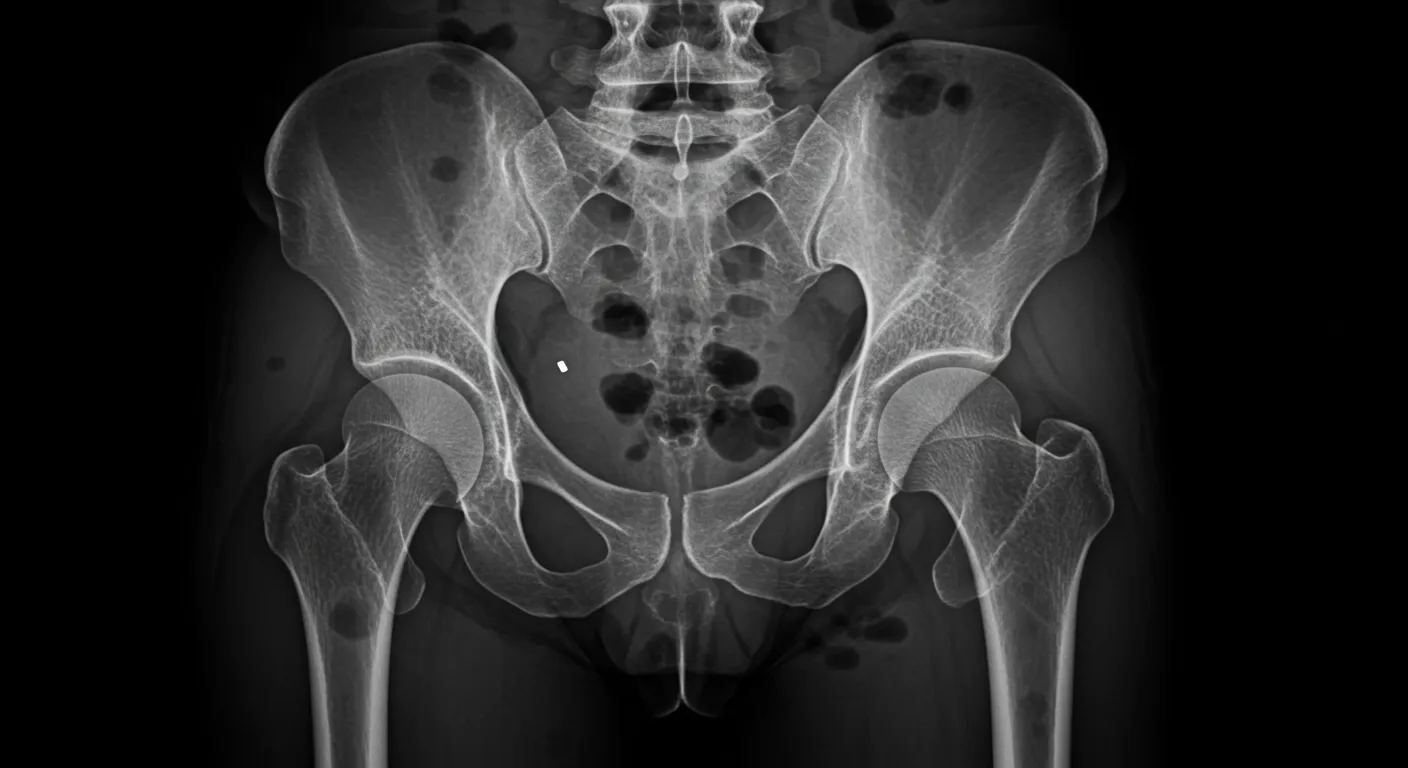

- Method: Bone mineral density measured using DEXA (spine L2–L4 and total femur)

- Femur BMD and T-score: No significant difference